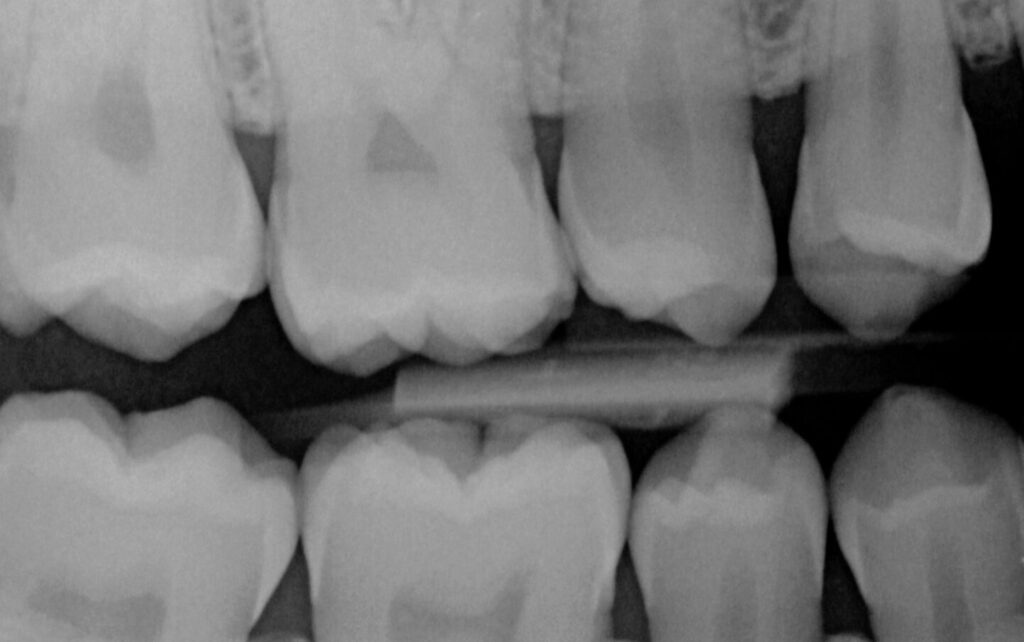

16 year old patient presented for standard recall examination. The patient had dental sealants placed on all 6’s when she was 7 years old, and all 7’s when she was 12 years old.

Minimal sealant localized just to the deepest grooves on her molars can be seen, with no excess. Marginal seal even on the 6s was still intact and smooth, with no signs of break down or recurrent decay. A case done right!